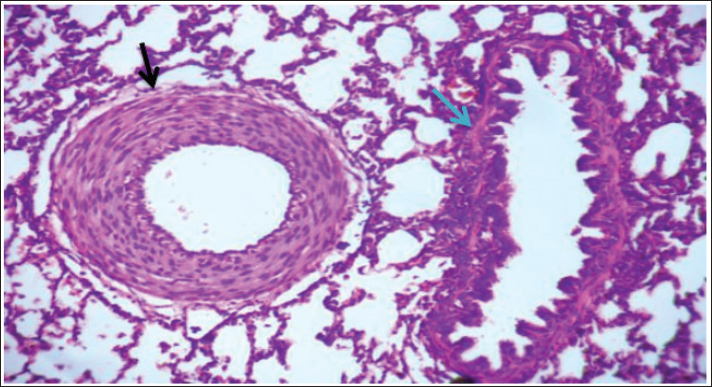

Histological examination of lung tissue revealed emphysema and atelectasis (Fig. 6A and B). Emphysema was characterized by permanent enlargement of air spaces distal to the terminal bronchioles, accompanied by destruction of alveolar walls without significant fibrosis.

Fig. 6. Group of infected rabbits lung (A) Bronchiols show emphysema aggregation of lymphocytic cell (black arrow)( B) show emphysema structure atelectasis (black arrow) H&E stain 400X and lung H&E stain 200X.

Fig. 7. The lung is show emphysema group of infected rabbits show moderate fibroplasia of arterioles. (black arrow) and tertiary bronchioles (blue arrow). H&E stain 400X (Castro et al., 2001).